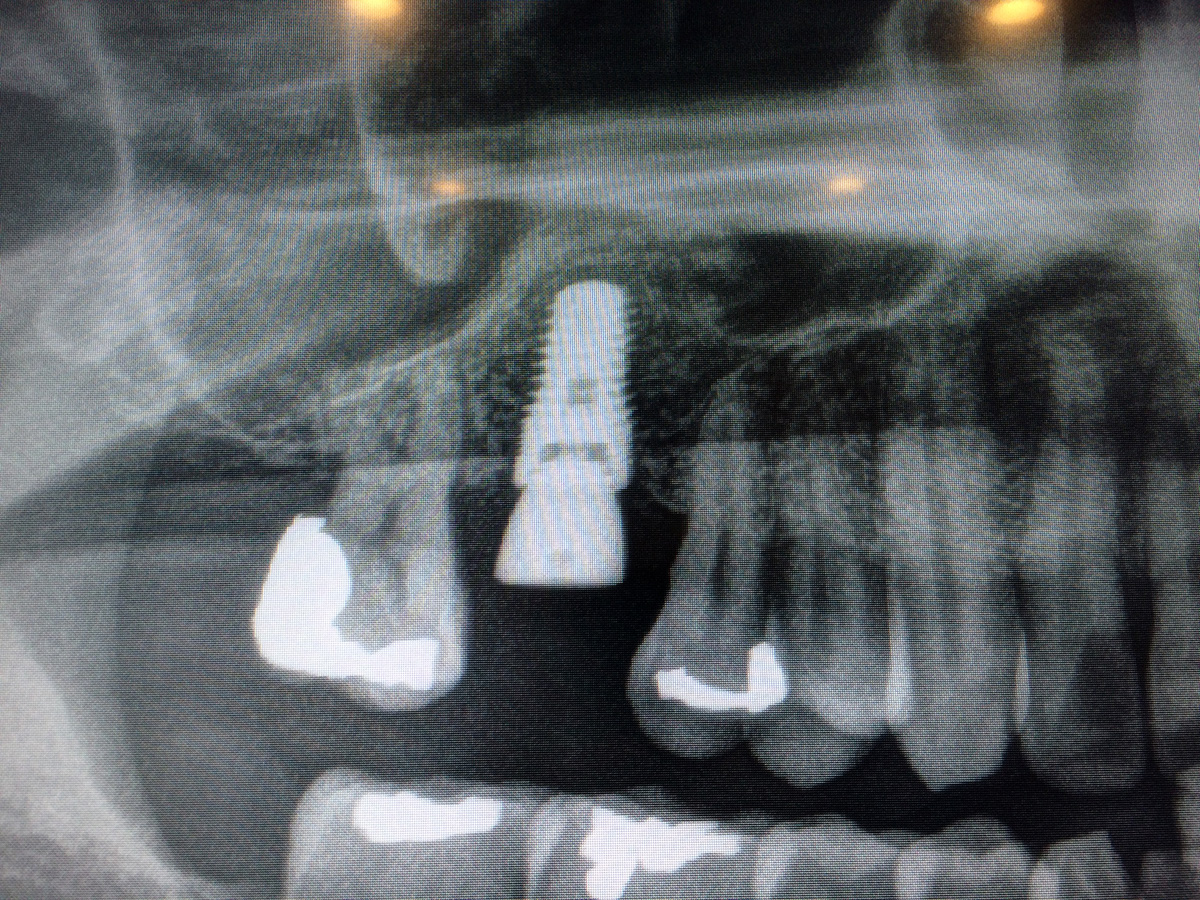

oral evaluation (11/14) panoramic x-ray (11/14) tooth removal (12/14) bone graft (12/14) periapical x-ray 2x (5/15) sinus lift with bone graft (5/15) dental implant (5/15) (crossed out prices meant paid through regular health insurance) |

$100 $850 $1950 |